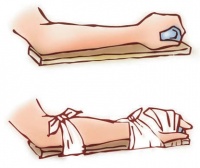

固定脱臼部位是减轻疼痛最佳的方法,自救的方法可用杂志,厚报纸或纸板托住手肘,另外使用三角巾,将手肘固定在胸部,就可以避免肩关节的活动,减少疼痛。禁止进食,因为可能需要全身麻痹治疗,可以聊天方式分散病患注意力,以减少其痛觉,另使用冰敷减少病患疼痛及肿胀,若要移动病患,尽量让她自己动,若其无法自动,则以托手肘及腕部来帮忙他,同时可用一个小枕头或软垫,置放在病患伤侧上肢内侧及胸部之间。